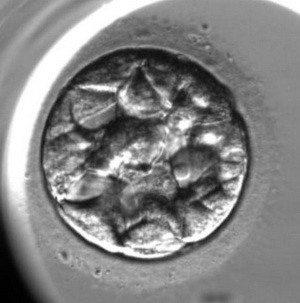

L’enregistrement du développement de l’embryon est le suivant :

Pour l’évaluation de la qualité des embryons on utilise la méthode d’analyse morphologique. Les embryons sont évalués selon les critères suivants : la quantité des blastomères, l’égalité des blastomères et la présence de fragmentation (des blastomères normaux qui ont été détruits). Cependant, cette méthode qui est la plus ancienne a ses inconvénients, elle est subjective (elle dépend de l’expérience et du niveau de l’embryologiste), un embryon est extrêmement variable durant son développement un embryon de mauvaise qualité de deux jours peut se transformer en un bel enfant en bonne santé. En ce moment, on utilise une nouvelle méthode d’évaluation de la qualité des embryons c’est l’embryoscopie. Son principe est le suivant : toutes les 10 ou 20 minutes on prend une photo de l’embryon en 7 couches, avec l’utilisation d’un programme informatique, on applique les images l’une sur l’autre pour en faire une video, c’est « le résumé » de chaque embryon. Avec l’utilisation d’un programme informatique spécifique, on mesure les paramètres clés du développement embryonnaire :

Le commencement du compactage de l’embryon